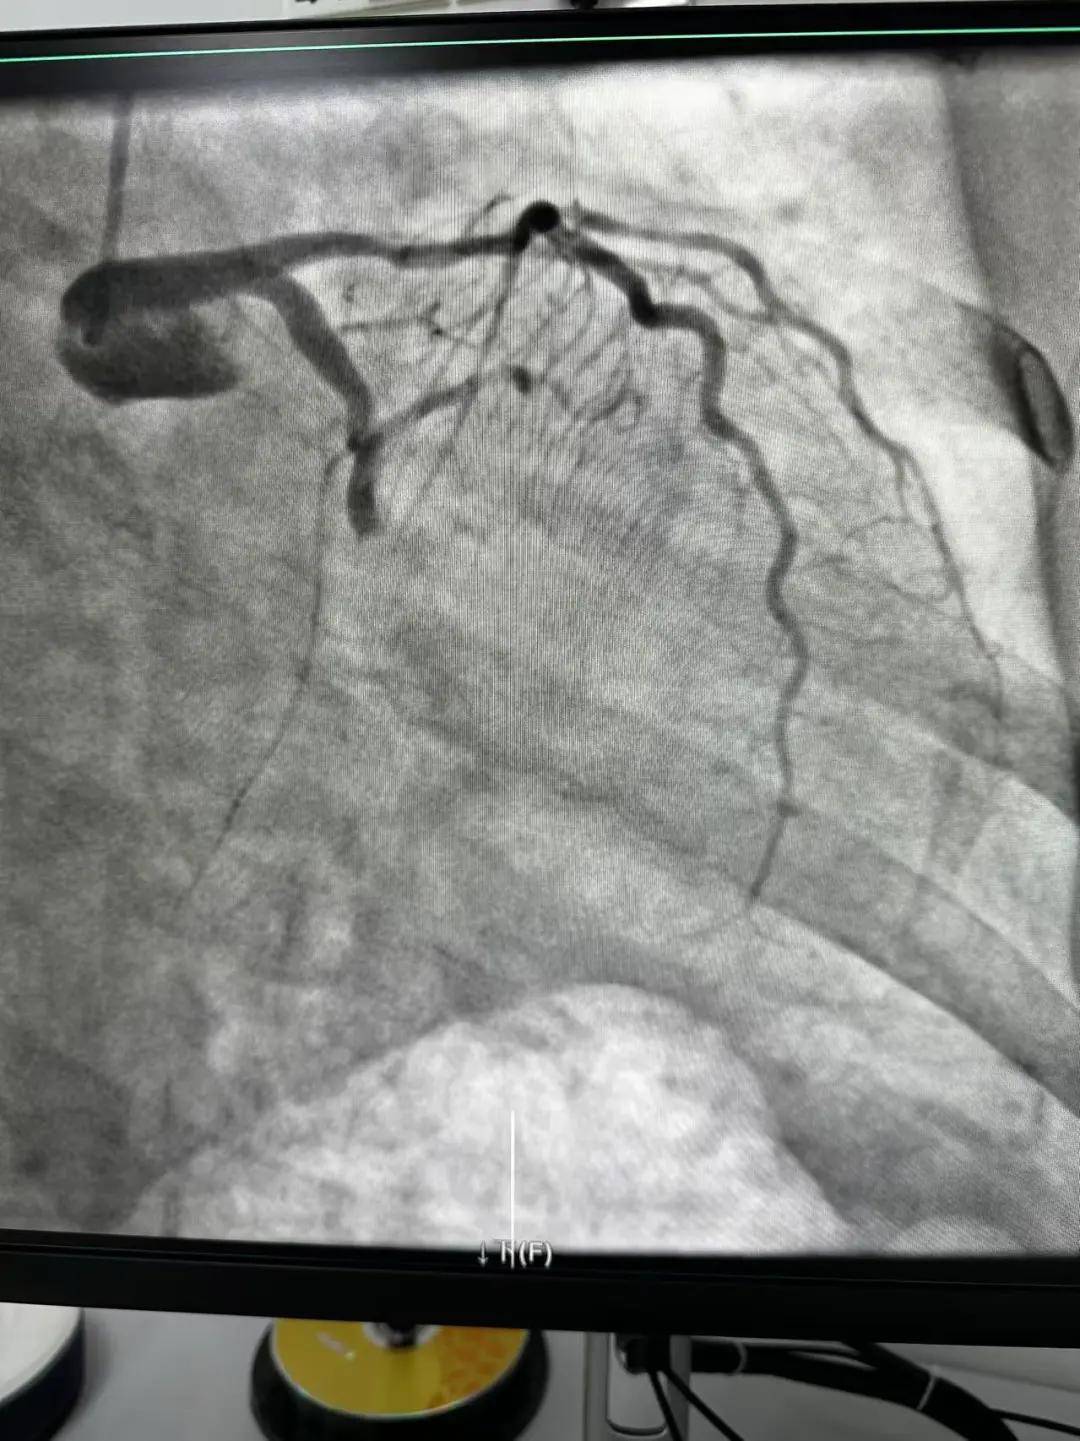

今天最后一臺手術(shù),是一個嚴(yán)重三支病變的病人,患者張大爺,71歲,以“突發(fā)胸悶胸痛3小時(shí)”為主訴入院。經(jīng)心電圖檢查后示室上性心動過速,以“冠心病、心絞痛、心律失常”為診斷收住入心內(nèi)科。心內(nèi)科團(tuán)隊(duì)通過審慎評估,決定給予患者冠狀動脈造影術(shù)及冠狀動脈內(nèi)支架置入術(shù)。

手術(shù)開臺,在王云峰主任的帶領(lǐng)下,心內(nèi)科團(tuán)隊(duì)為張大爺進(jìn)行穿刺。由于病人重聽,在手術(shù)臺上配合度不高,加上病情嚴(yán)重,導(dǎo)致手術(shù)難度加大。手術(shù)正在緊張進(jìn)行中,導(dǎo)管室內(nèi)線電話又急促響起!一位急性心肌梗死患者情況危急,需要緊急進(jìn)行介入治療。

許先生,52歲,大貨司機(jī),在鶴壁至安陽卸貨過程中,突發(fā)胸悶胸痛,伴大汗1.5小時(shí)。 患者繞行安陽,于11點(diǎn)38分到達(dá)我院大門,11點(diǎn)41分首份心電圖,提示患者下壁心肌梗死。 起病急,病程短,情況十分危險(xiǎn),如果血管完全堵塞將直接威脅患者生命,亟需疏通堵塞血管進(jìn)行血運(yùn)重建。

穿刺、造影、放支架……兩個手術(shù)間各個環(huán)節(jié)緊張卻有序地進(jìn)行著!在心內(nèi)科團(tuán)隊(duì)精準(zhǔn)、默契的配合下,兩臺手術(shù)順利完成! 兩名患者的快速、同時(shí)、成功救治,得益于殷都區(qū)人民醫(yī)院醫(yī)務(wù)人員快速的應(yīng)急能力、過硬的急救技能,同時(shí)更得益于導(dǎo)管室同開臺,保障了救治的迅速有效。